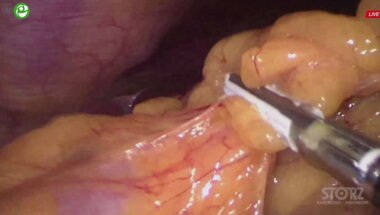

Ефанов, Казаков - Лапароскопическая гастрэктомия с лимфодиссекцией D2

Санжаров А.Е, Галлямов Э.А. - Лапароскопические междисциплинарные вмешательства